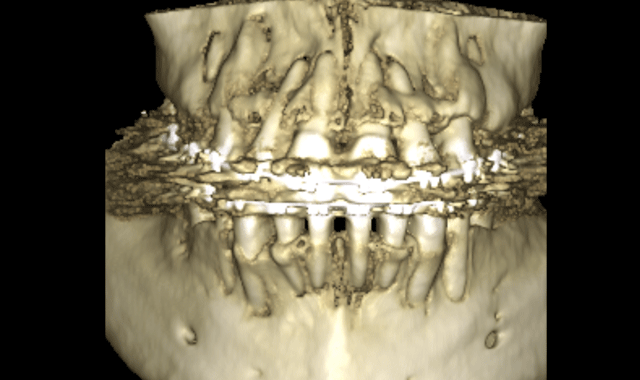

Note in Figure 3 how the roots seem to be violating at the cortical bone of the alveolar housings. The thickness of this slice is 5mm. Figure 4 is the 3D rendering of the same scan. The brackets placed on this patient had a -6 degree torque. Perhaps this patient would have been better served with -1 degree torque. The upper incisors had a 17 degree torque. Perhaps more torque would have kept the roots of the teeth of the upper incisors in the alveolar housing. This is just one simple example of how the specialty must start looking at the anatomy of our patients.

Fig. 4